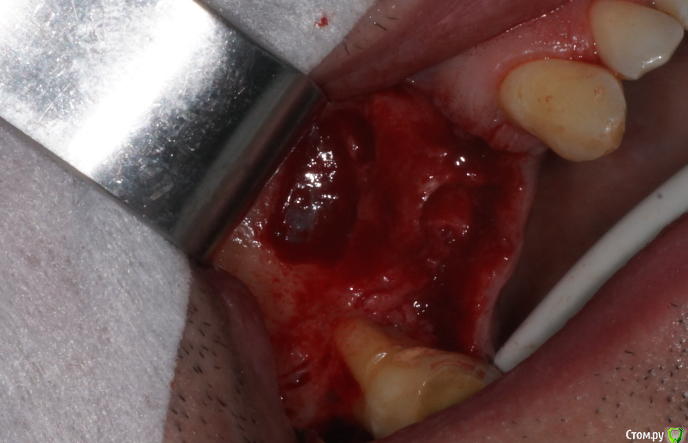

В день вмешательства обрадовала ассистент - оказывается заказ "открытый синус лифт" еще не предполагает заказа на комплект гладилок. Сетевые клиники такие сетевые. Пришлось дедовским способом - турбинка, серповидная и распатор.

В начале планировал три имплантата, между зубами - 18,5 мм, в притык. Когда делал анестезию посмотрел наконец-то в рот (не смейтесь, внимательно посмотрел) - подумал, что моляр и два премоляра ортопед может не всунуть. Короче, передумал и решил ставить два и если че - пусть мостик или консоль делает.